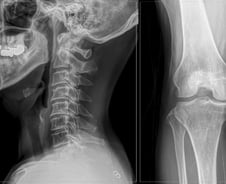

척추·관절 질환은 하나의 병이 또 다른 병을 부르는 경우가 다반사다. 한 부위에 이상이 생기면 이를 보완하기 위해 다른 부위에 연쇄적으로 부담이 가기 때문이다. 허리 통증으로 병원을 방문했다가 무릎의 문제가 더 심해 먼저 치료받기도 한다. 특히 고령층은 퇴행성 변화로 두 부위에서 동시에 통증이 나타나는 경우가 잦다. 바른세상병원 척추센터 박재현 원장(신경외과 전문의)은 "척추와 관절 치료를 병행하는 환자는 10명 중 6명 정도"라고 말했다. 두 병을 함께 앓는 '중복 질환'은 의사라고 해도 쉽게 알아차리기 어렵다. 정확한 진단을 위해 각 분야의 세부 전문의들이 머리를 맞대고, 유사한 증상의 질환을 종합적으로 검토해 치료법을 선택해야 한다. 현대인을 괴롭히는 대표적인 중복 질환을 박재현 원장의 도움말로 알아본다. ━척추관협착증과 퇴행성관절염━척추관협착증은 척주관이 좁아지면서 신경을 압박하는 질환이다. 주요 원인은 노화로 50~60대 이후 나이가 들수록 발병률이 증가한다. 척추관협착증